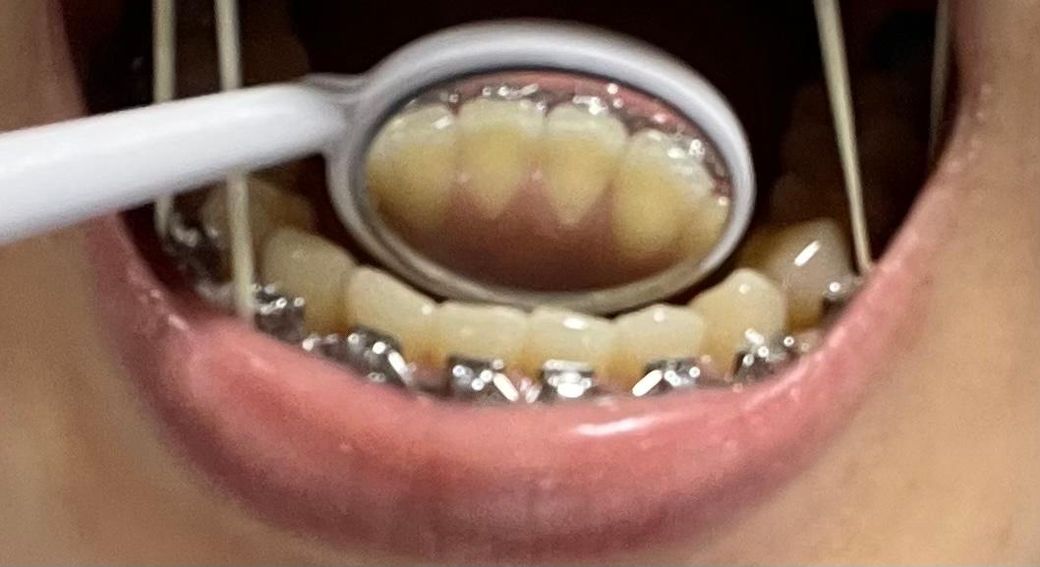

그리고 2,3번째 사진은 현재인데, 평소에 신경 안쓰고 살다가 우연히 보게 됐는데 아랫니 치아 안쪽 잇몸이 너무 v자로 파진 느낌이 드는데 원래 그런건가요?

• 2번 째 사진

방사선 사진 상에서 치근 길이 엄청 짧거나 이상있어 보이지는 않으며 구내 사진 상에서도 큰 이상은 없어보입니다. 교정 치료 중에는 치아 이동에 따른 치근 흡수가 발생할 수 있으며 교장 합병증 중 하나입니다.

지금 첨부 주신 사진상에서는 큰 이상은 없어보입니다. 너무 걱정하지는 않으셔도 될 것 같으며 자세한 것들은 사진 자료가 있는 교정 치과에서 꼭 이야기 나눠보시기를 바랍니다.